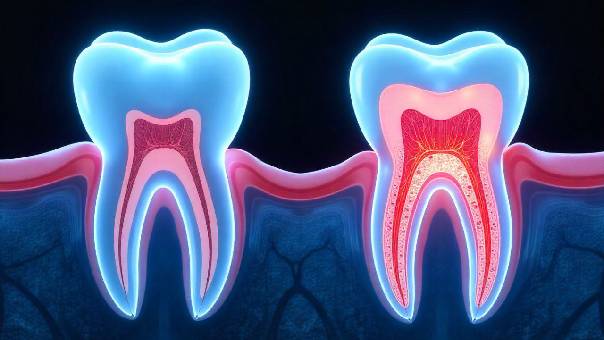

What is a Root Canal Treatment?A root canal treatment is a dental procedure designed to remove infected or damaged pulp tissue from within a tooth. The pulp is the innermost part of the tooth, containing nerves, blood vessels, and connective tissue. When it becomes infected due to deep decay, cracks, or trauma, it can cause severe pain, swelling, and eventually lead to tooth loss if left untreated.

The goal of RCT is to clean the infected area, disinfect the canals, and seal them to prevent further bacterial invasion. This allows the tooth to be preserved rather than extracted.